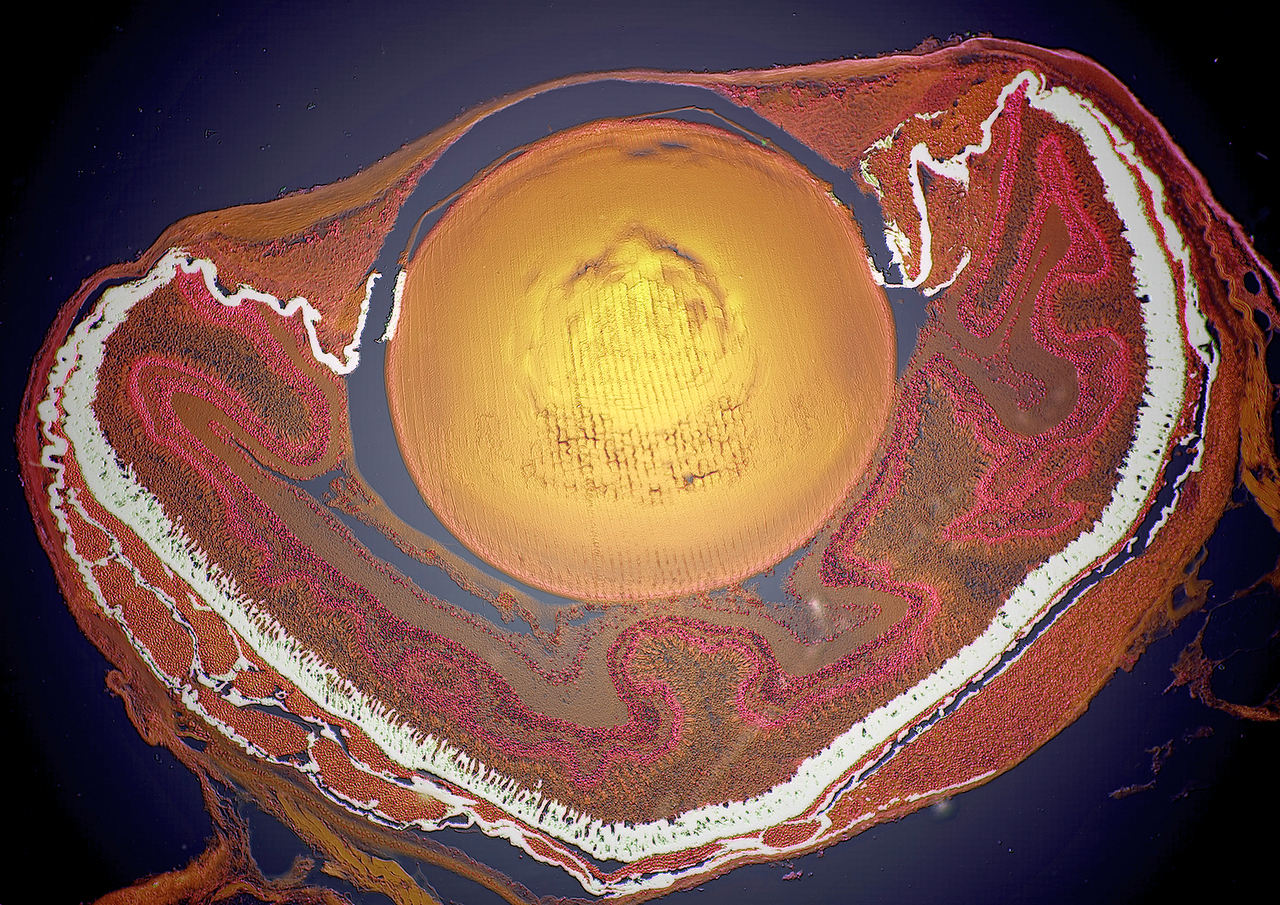

Глаз кролика в разрезе

Гистологический препарат под микроскопом

Ключевые слова: Глаз кролика в разрезе